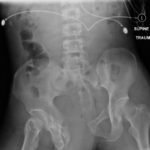

Open Book Pelvic Fracture

A 31-year-old male was brought in by paramedics status post high-speed motorcycle collision. The patient was tachycardic and hypotensive with an initial Glascow coma scale (GCS) of 11. He required immediate blood transfusion and intubation. The patient had multiple traumatic injuries including a deformity to the left thigh and an unstable pelvis. He had palpable distal pulses, and grossly normal sensation and motor function to his bilateral lower extremities.

The initial radiograph of the pelvis shows an open-book pelvic fracture deformity with pubic symphyseal dislocation, left greater than right sacroiliac diastases, and fractures of the left superior and inferior pubic rami, right inferior pubic ramus, and left acetabular anterior column. The additional inlet and outlet radiographs of the pelvis after application of a pelvic binder also show an open book fracture with significant improvement of the widened pubic symphysis.